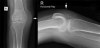

4) Very Large

This elderly patient fell onto her right knee.

She has sustained a fractured patella and has a very large knee joint effusion (arrowed).